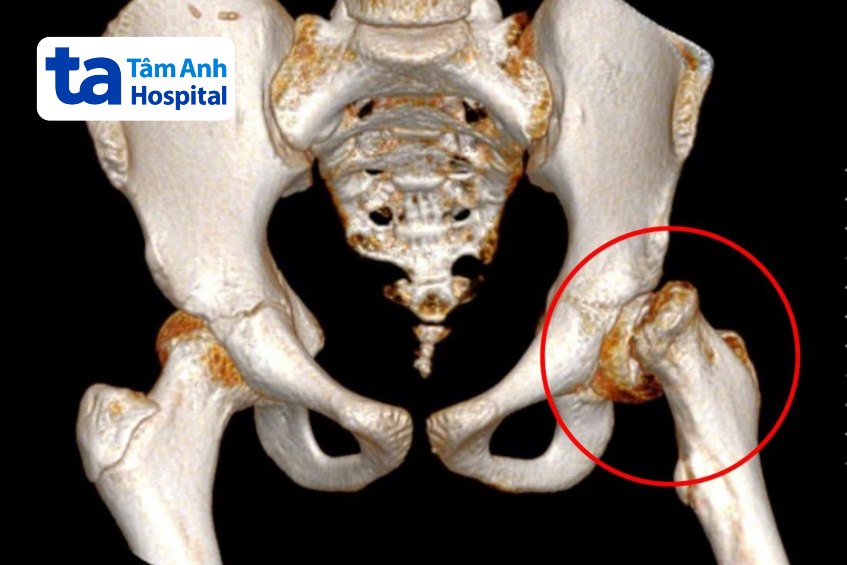

Chenda bắt đầu đau khớp háng bên trái vào hai tuần trước nhưng vẫn đi lại bình thường. Khi cơn đau trở nên nghiêm trọng, em nằm bất động, không thể giạng chân hay thực hiện bất kỳ cử động nào, gia đình đưa đi khám và chuyển viện sang Việt Nam. Kết quả chụp CT tại Bệnh viện Tâm Anh cho thấy chỏm xương đùi của bệnh nhi gần trượt hẳn ra ngoài.

Bác sĩ Trường cho biết trượt chỏm xương đùi là tình trạng chỏm xương đùi trượt ra khỏi cổ xương đùi, thường gặp ở trẻ trong giai đoạn dậy thì. Hiện vẫn chưa xác định được chính xác nguyên nhân gây trượt chỏm xương đùi ở trẻ em.

Với đường mổ làm trật khớp háng, cho phép bác sĩ làm trật khớp háng ra ngoài nhưng vẫn bảo tồn mạch máu nuôi. Điều này tạo điều kiện cho bác sĩ quan sát rõ vùng chỏm xương đùi để thực hiện chính xác thao tác bóc tách và loại bỏ các mảnh xương gãy vỡ. Ca phẫu thuật kết thúc sau 5 tiếng, các mảng xương thừa được loại bỏ hoàn toàn, đảm bảo không tì đè làm tổn thương mạch máu. Chỏm xương đùi của bệnh nhi cũng được nắn chỉnh lại đúng vị trí và cố định bằng 2 đinh ốc, thêm 2 đinh ốc cố định mấu chuyển lớn.